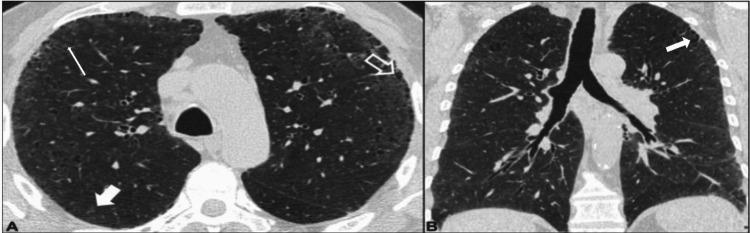

Introduction Interstitial lung diseases (ILDs) primarily affect the interstitium, an alveolar wall tissue between the capillary endothelium and the alveolar epithelium. The term 'interstitial,' however, is misleading since alveolar spaces, peripheral airways, and vessels can be involved in most of these disorders.They often require a multidisciplinary diagnosis i.e., an integration of clinical, radiological, and pathological findings. A chest radiograph is relatively insensitive because of nonspecific patterns. Generally, these disorders can progress to irreversible pulmonary fibrosis and are an important cause of morbidity and mortality. It is critical to make a prompt and accurate diagnosis of the underlying causes so that patients can be managed appropriately. ILD is subdivided into idiopathic interstitial pneumonia, of which idiopathic pulmonary fibrosis (IPF) is one subset, and diffuse parenchymal lung diseases, which may be secondary to a variety of occupational or environmental exposures or others. They can complicate multiple rheumatic or connective tissue diseases (CTDs). Apart from ILD, other forms of lung damage involving the pleura, vasculature, airways, and lymphatic tissue can complicate CTDs. Aims  Aims include studying the role of high-resolution computed tomography (HRCT) in diagnosing various ILDs based on morphologic patterns, evaluating the correlation between ILD and various connective tissue disorders and the prevalence of complications in such patients, and evaluating the association of smoking with various ILDs. Methods This is a retrospective study in which HRCT thorax was performed on a 128-slice Philips CT scanner machine on 50 patients from December 2020 to February 2022 in SVP Hospital, Ahmedabad. No age or gender bias was followed. Result Out of 50 patients studied, 19 (38%) patients had the usual interstitial pneumonia (UIP) pattern and 12 (24%) had the nonspecific interstitial pneumonia (NSIP) pattern. These two were the most common among all ILD patterns. Other patterns found were hypersensitivity pneumonitis (5; 10%), respiratory bronchiolitis-related ILD (3;6%), and organizing pneumonia (2; 4%). In nine patients, the morphologic pattern was either subtle (3; 6%) or mixed (6; 12%), and the final diagnosis remained inconclusive; patients were advised clinical correlation and biopsy. Eleven (22%) patients had a history of smoking. Among smokers, the most common pattern was UIP while all patients with respiratory bronchiolitis (RB) ILD had a history of smoking. Fourteen (28%) patients showed a positive association with CTD. Among them, rheumatoid arthritis (RA) was the most common CTD and the most common pattern among RA patients was UIP. Ten (20%) of patients developed pulmonary arterial hypertension, of which two patients who had connective tissue disorder developed pulmonary arterial hypertension at a young age (24 years). The rest of the patients who developed pulmonary arterial hypertension were above 45 years of age. Among these, two were smokers. Conclusion HRCT plays an important role in the diagnosis of ILD on the basis of various morphological patterns. CTD plays a significant role in the development of ILD. UIP is the most common ILD among patients with a smoking history and RA. NSIP Is the most common in patients with CTD other than RA. Pulmonary arterial hypertension (PAH) develops early in patients with CTD. There is a significant risk of the development of PAH in patients with chronic ILD.

在研究的50例患者中,19例(38%)表现为普通型间质性肺炎(UIP)模式,12例(24%)表现为非特异性间质性肺炎(NSIP)模式。这两种是所有ILD模式中最常见的。发现的其他模式包括过敏性肺炎(5例;10%)、呼吸性细支气管炎相关的ILD(3例;6%)和机化性肺炎(2例;4%)。9例患者的形态学模式不明显(3例;6%)或为混合型(6例;12%),最终诊断仍不明确;建议患者进行临床关联和活检。11例(22%)患者有吸烟史。在吸烟者中,最常见的模式是UIP,而所有呼吸性细支气管炎(RB)ILD患者都有吸烟史。14例(28%)患者显示与CTD呈正相关。其中,类风湿关节炎(RA)是最常见的CTD,RA患者中最常见的模式是UIP。10例(20%)患者发生了肺动脉高压,其中2例患有结缔组织病的患者在年轻时(24岁)发生了肺动脉高压。其余发生肺动脉高压的患者年龄在45岁以上。其中,2例为吸烟者。